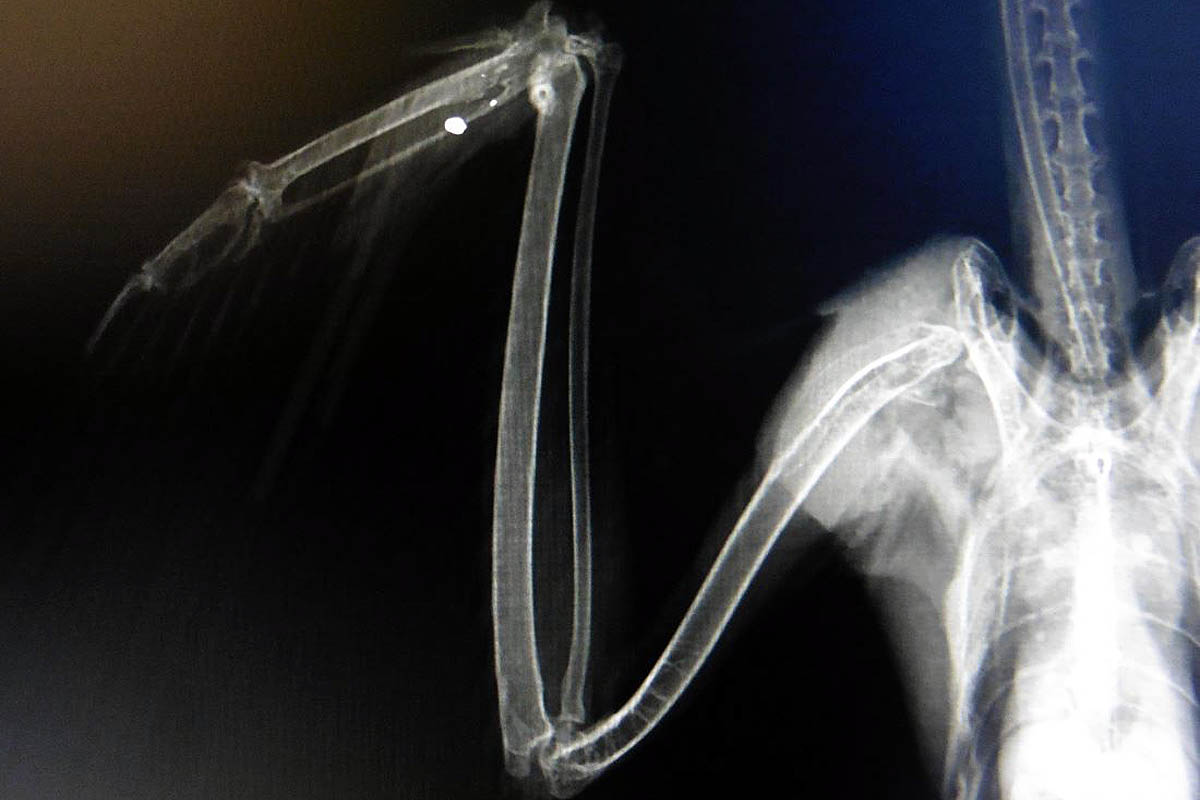

bat wing xray Bat wings, Bat anatomy, Bat Broken Bird Wing X Ray Identifying a broken wing effectively can ensure that the bird receives the appropriate care it needs. Here are the most common signs of a broken wing in birds: Look for any unnatural positioning of the wing or any visible bumps, bruises or swelling which may signal a fracture or. Improper positioning and/or radiographic technique can underestimate or overestimate potential lesions.. Broken Bird Wing X Ray.